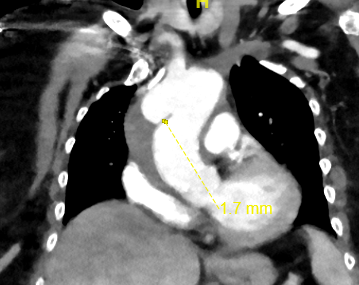

Other than that there really isnt anything else to say other than the usual. PMS in the groins for a pump, else axil impella, loads of dob, vaso probably epi here too plus probably nitric, straight onto dialysis the second he stops peeing. A good perfusionist that will take plenty volume off him. Mitral Probably repairable with a ring.

We have to look at the tricuspid too though with a right that big even off axis